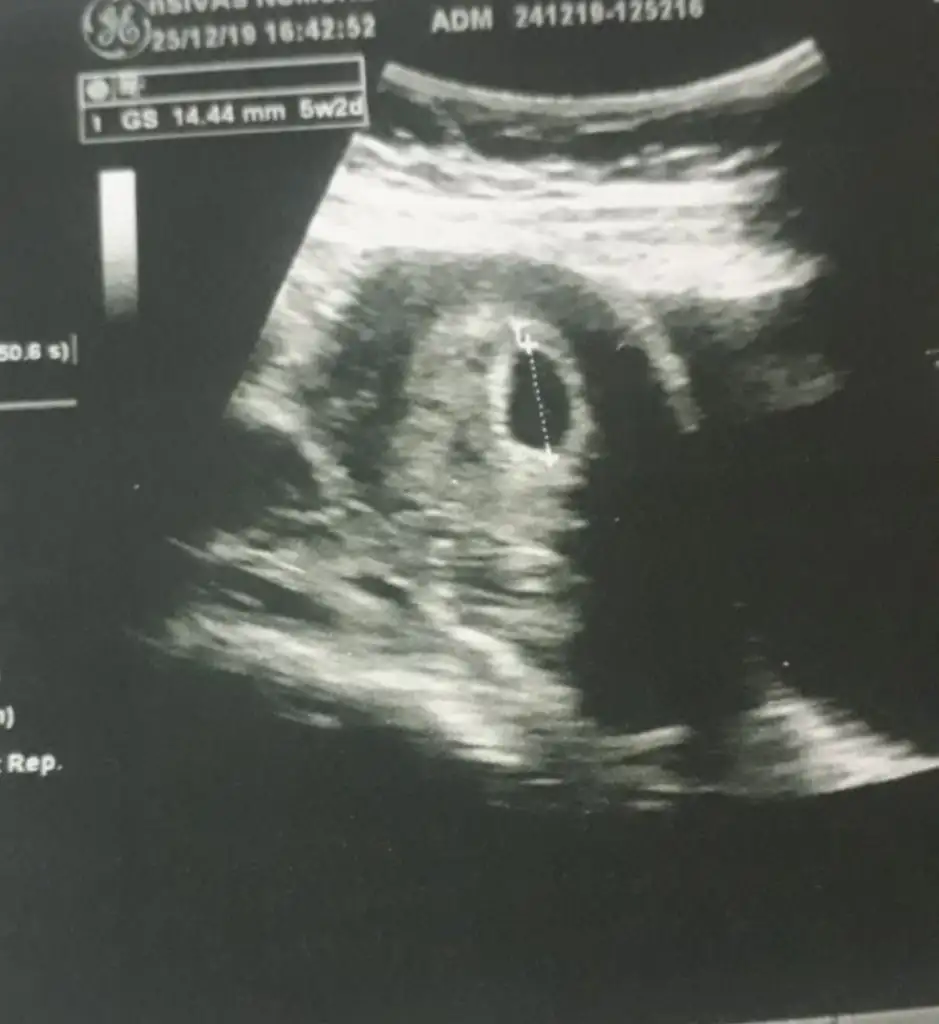

Yolk sac Sagda buna göre kız 7 haftanızıda paylaşınMerhaba 5+4 hamileyim. Karından bakıldı. Bişey anlaşılırmı bi bakarmısınız?

Onlar yok malesef 5+2 var 1 2 sayfa önce paylaşmıştım 9 hafta olan da bugün çekildi6+ olmalı kese için yada 11 hafta 12 hafta nub için paylaşın

Yolk sac solda karından bakıldıysa yolk saca tutunuyor bebek buna göre erkekEki Görüntüle 2576955 5+2 sadece kese var bebek görünmüyor keseye göre var mı bi tahmini olan?